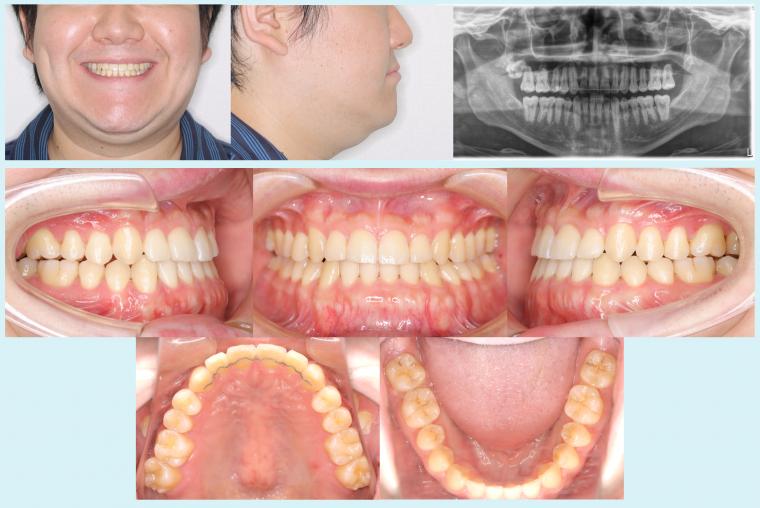

#46 下顎歯列の後方移動を行った症例